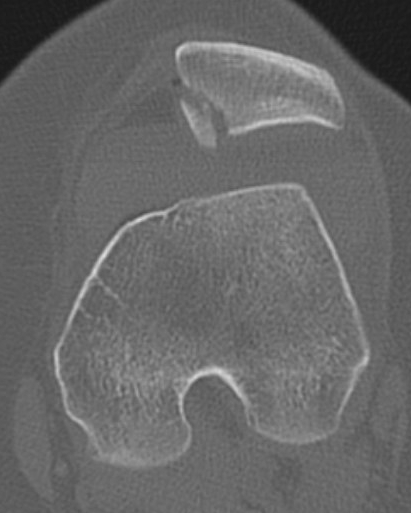

CT

Osteochondral fracture of the lateral femoral condyle

Large osteochondral fracture medial facet patella

Large osteochondral fracture lateral femoral condyle